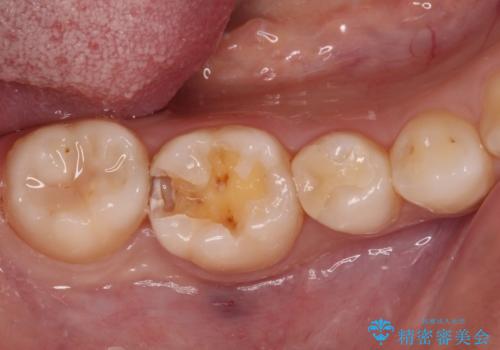

- 近々海外へ転居するとのことで、事前に処置をしておくべきむし歯がないか、気にして来院された患者様です。

レントゲン写真などから、速やかに処置を行うべき歯が2歯あったため、それぞれセラミックインレーとPGAインレー(ゴールドインレー)にて修復治療を行うこととしました。

どちらの歯も痛みなどの症状はなく、治療後も異常所見なく経過をたどっています。